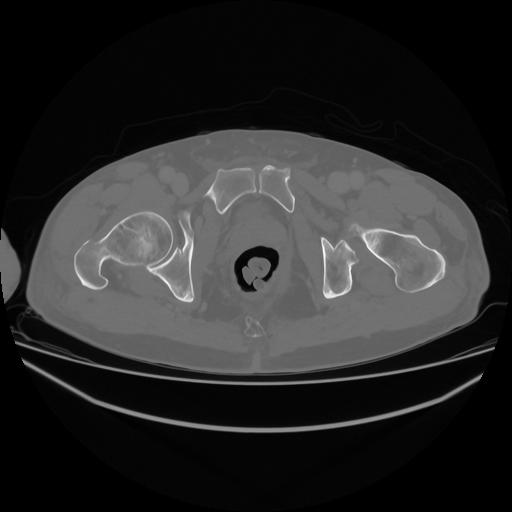

5 CUERPO,CE,Vol,1.0,CUERPO,,